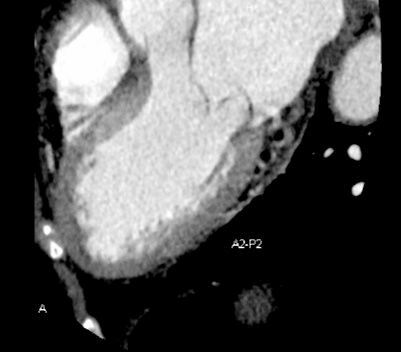

Computed tomography (CT) has emerged as an important adjunctive imaging modality for mitral valve surgery, offering precise anatomical measurements and 3D reconstruction capabilities [74]. CT enables detailed assessment of mitral annular dimensions, leaflet thickness, and spatial relationships with adjacent cardiac structures (Fig. 3).

Fig. 3.

Computed tomography imaging of mitral valve prolapse (P2) and annular dimensions.

Integration of CT and echocardiographic data through fusion imaging technologies has further improved procedural planning, device sizing, and intraprocedural navigation.